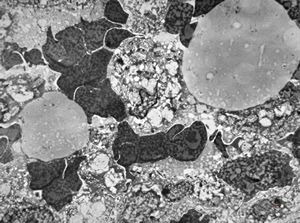

M,54y. | duodenum … Whipple disease, foamy histiocyte

lipid malabsorption